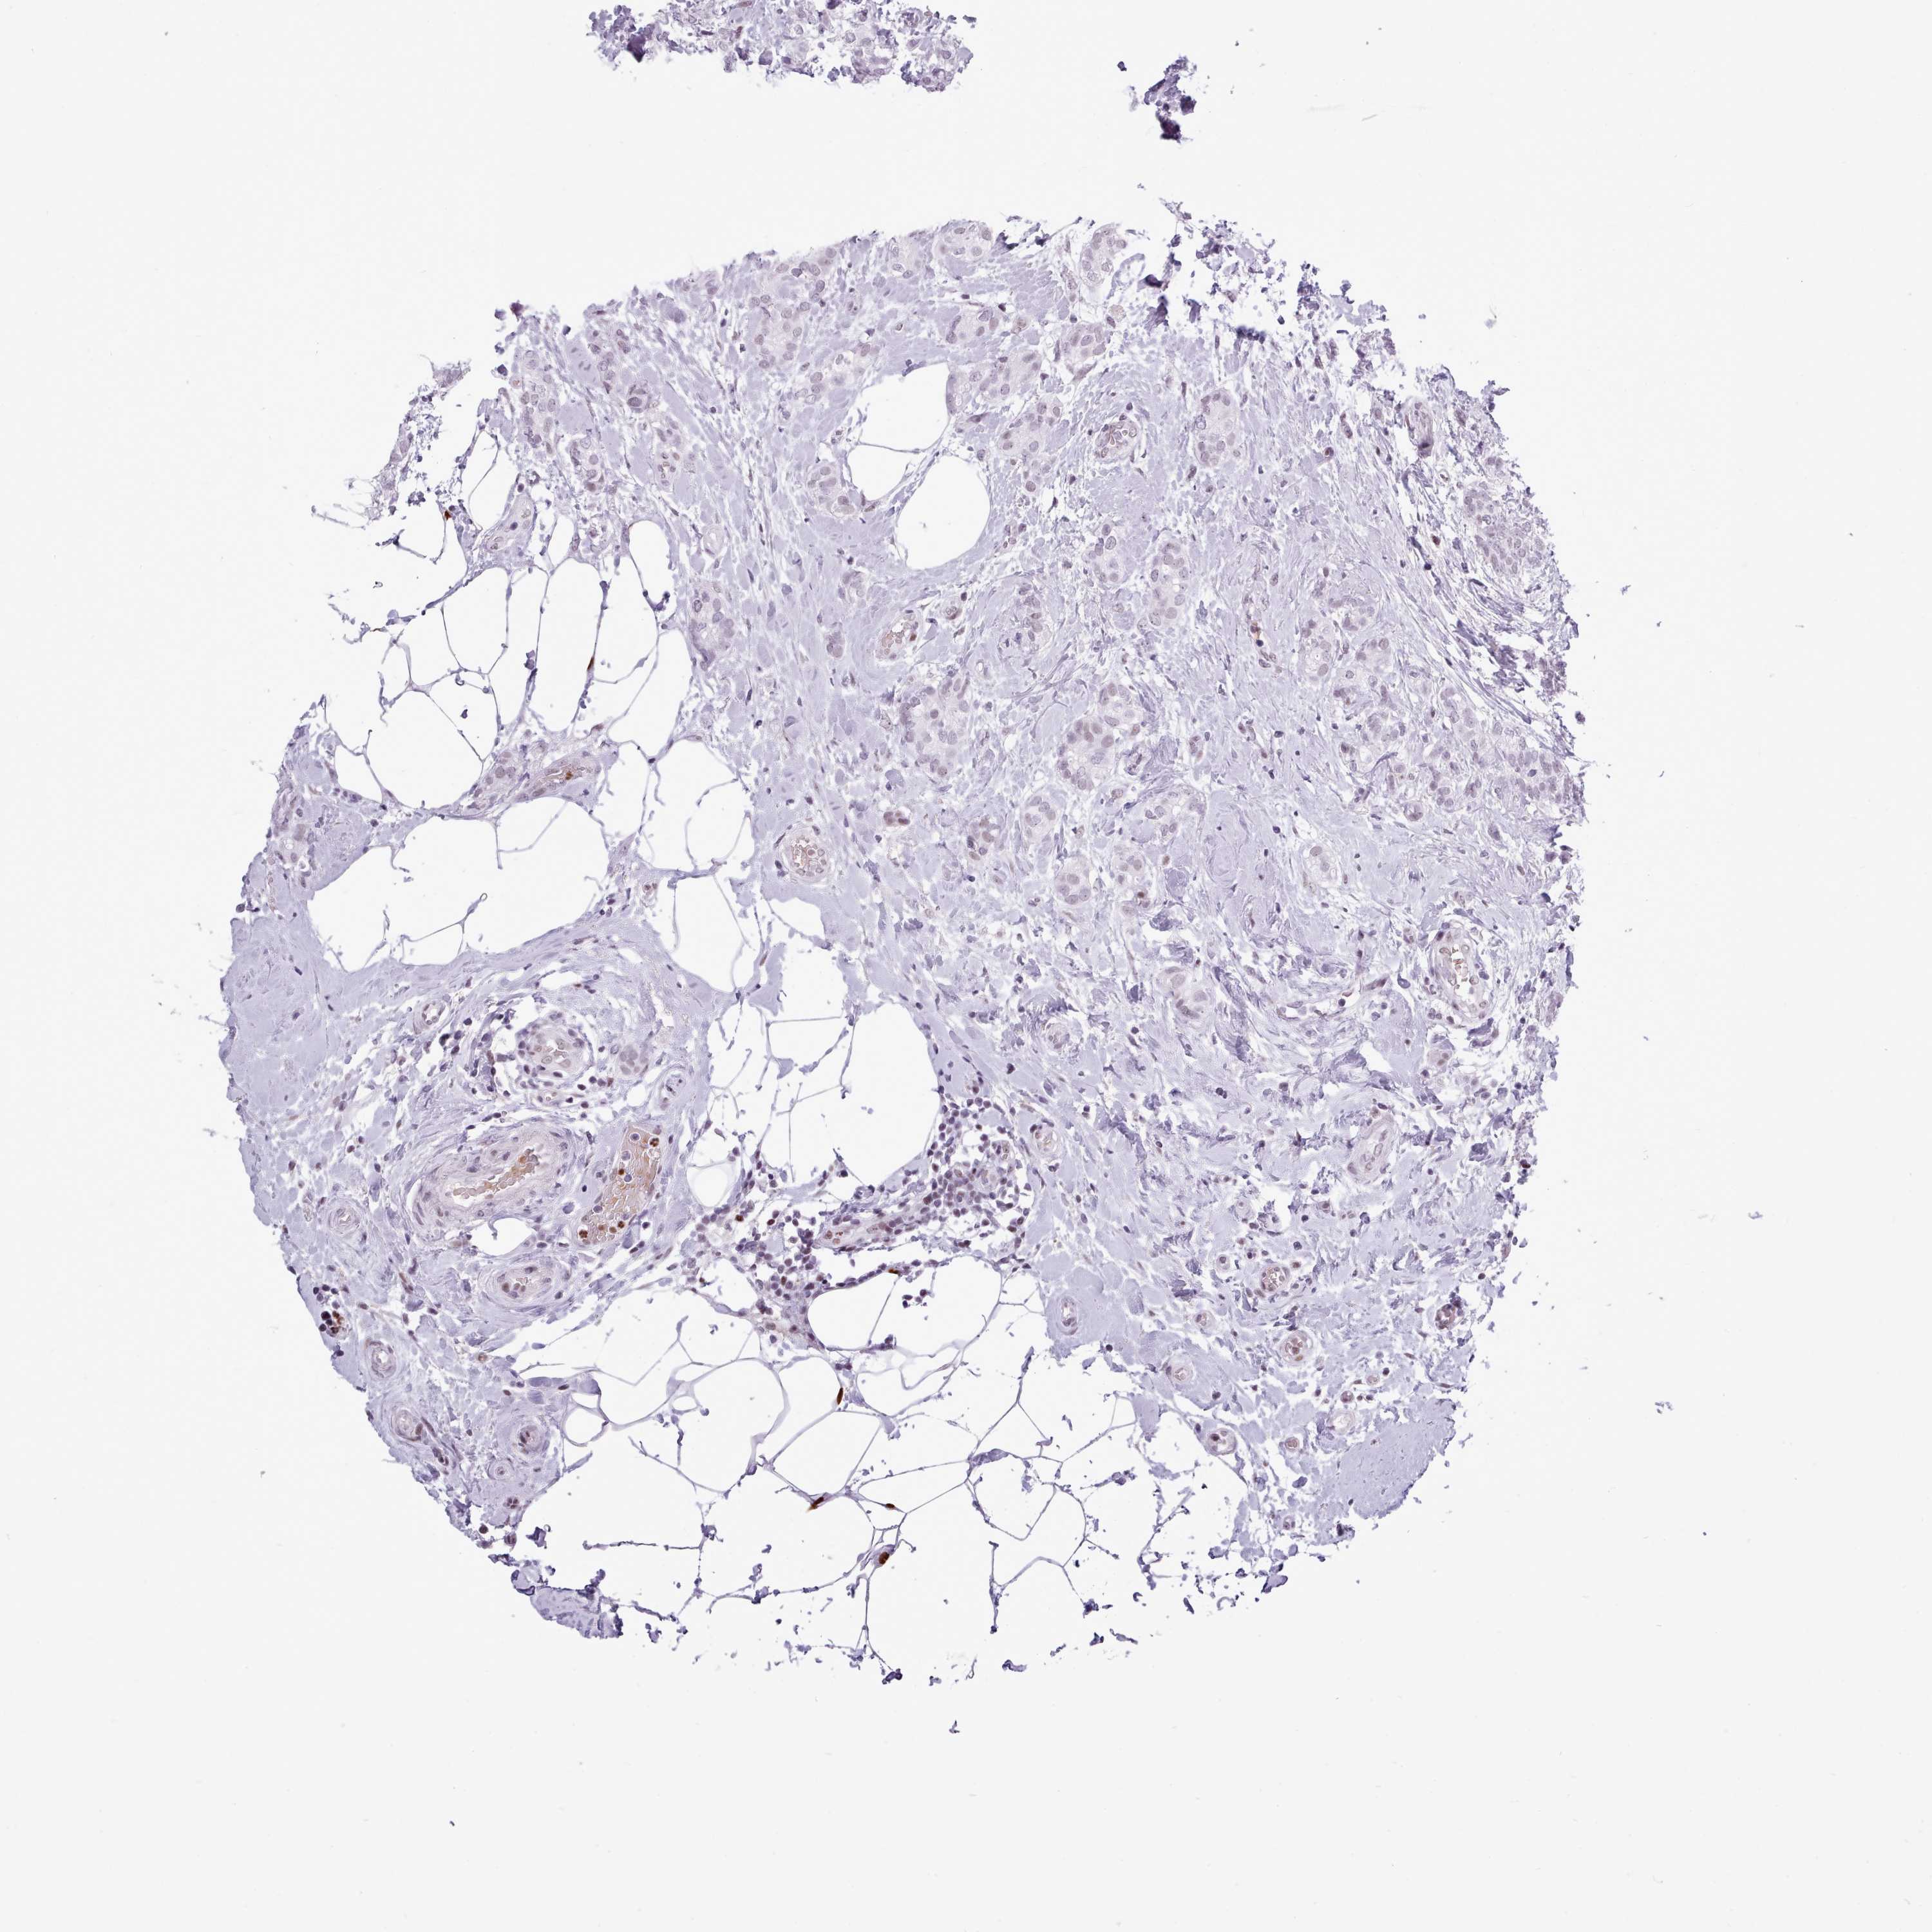

BRCA TCGA BRCA VALIDATION PROTEIN EXPRESSION

ANTIBODIES

AND

VALIDATION